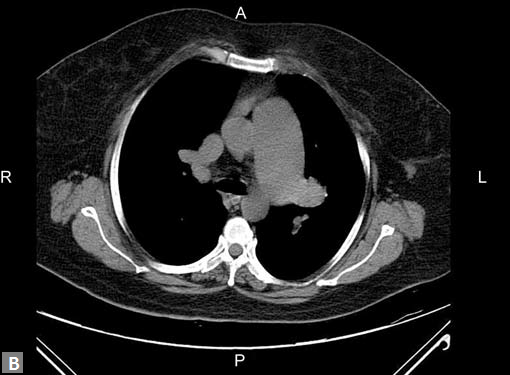

Filling defects (Figs 16A and B) may be seen in main

pulmonary artery (MPA), left pulmonary artery (LPA) and

right pulmonary artery (RPA), interlobar artery, segmental

divisions (Figs 17A and B). On occasions, detection in distal

parts of segmental divisions is difficult. This can be further

confounded by motion artifacts, non- or minimally opacified

accompanying pulmonary veins.